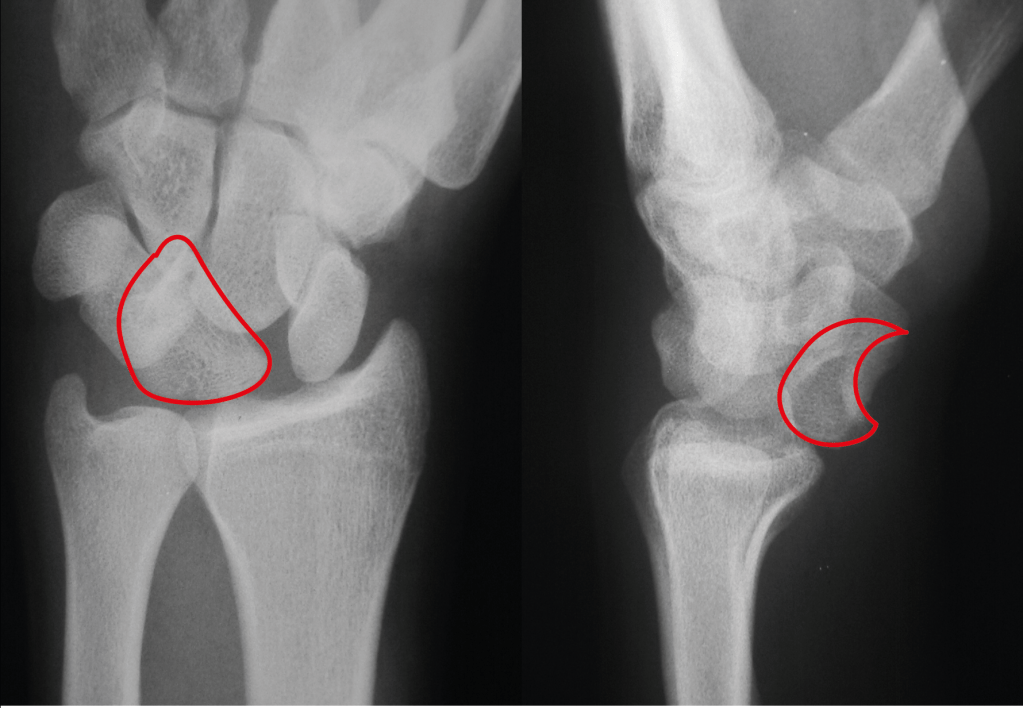

The bones of the wrist can be seen on the X-ray below:

This is a normal wrist X-ray. The lunate bone is outlined in red – this bone is named from “luna”, the latin word for moon – you can see on the right side view X-ray that the bone is shaped like a crescent moon on its side. The curve of the lunate points upward.